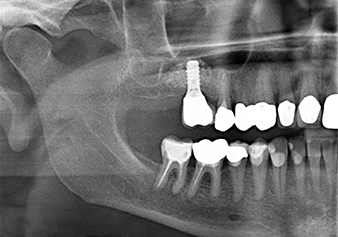

A 49-year-old female patient, a non-smoker and with nothing remarkable in her general medical history, was referred to our oral surgery practice for surgical extraction of tooth 16 and subsequent implantation. After the extraction, the patient experienced mild sinusitis trouble with the resultthat we initially waited six months before carrying out the measure. The residual bone height at the planned implant position measured 3-4 mm (Fig. 1 and 2).

The x-ray check shows a largely homogeneous peri-implant hard tissue structure

Fig.10: A good six months later, after the definitive crown had been incorporated, the x-ray check shows a largely homogeneous peri-implant hard tissue structure.